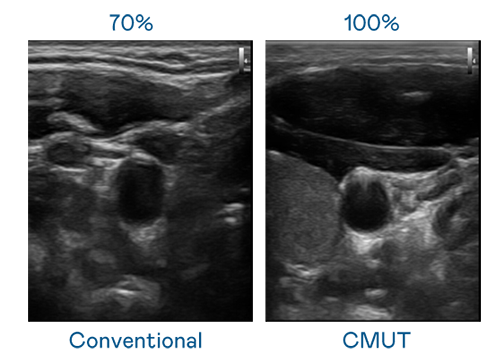

CMUT 技术是一种用电容式微机电元件来产生超音波讯号的技术。与传统 PZT 压电式技术相比,CMUT 频宽增加 30%,更宽频的超音波讯号让影像解析度大幅提升,是实现高影像品质医疗超音波扫描、促进精准医疗发展的关键技术。

超音波影像的解析度高低,首先取决于探头能发出的讯号频宽。XPJ CMUT 可提供高清晰的超音波讯号,提供高频宽、高灵敏度、影像纹理细节更高的超音波影像,协助医护人员缩短影像判读时间及利用精准的医疗影像进行诊断。